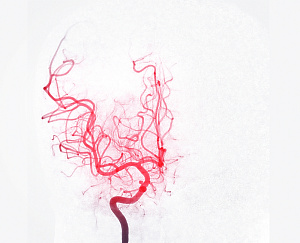

Кроме того, существуют методы объективного подтверждения миокардита:

• исследование биопсийного материала из миокарда правого желудочка и МЖП,

• МРТ сердца с контрастированием (выявление воспалительного интерстициального отека в миокарде),

• радиоизотопное исследование миокарда с радиофармпрепаратом , тропным к воспалению.